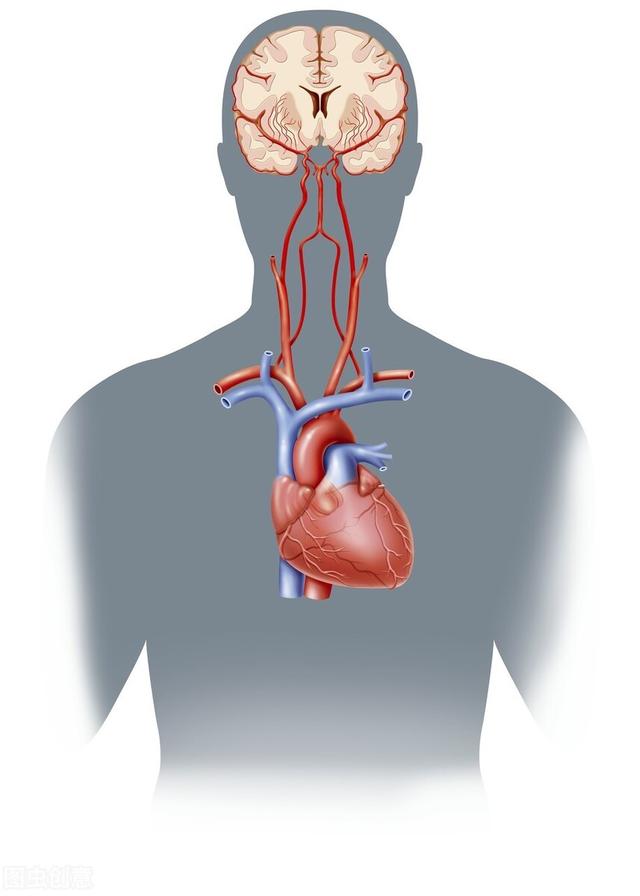

私たちの脳細胞は非常にデリケートで、エネルギーを蓄えることができず、新鮮な血液からの酸素とブドウ糖で生きている。脳への血液供給が滞ると、すぐに症状が現れ、数分以内に脳細胞が死に始め、不可逆的な損傷を引き起こす。

脳への血液供給は、主に首の前にある内頸動脈と首の後ろにある椎骨動脈という2本の血管から行われている。この2本が脳を正常に機能させるための生命線である。

内頸動脈は主に脳の最初の3分の2を供給している。

椎骨動脈は主に脳の後部3分の1と小脳に供給している。

脳への血液供給は、高層ビルの最上階への給水のようなもので、血管は水道管、心臓は送水ポンプのようなものである。脳への正常な血液供給には2つの鍵がある;血管が開き、心臓のポンプ機能が十分であること。.そして、脳への血液供給不足の臨床的原因には、主に血管の問題と心臓の問題の2つがある。

通常の状況下では、人間の脳の血液供給は非常に豊かで、静かな状態では、心臓が毎分70回鼓動する場合、心臓が収縮するたびに、左心室から血液の約70ミリリットルの大動脈に、毎分吐出血液の左心室は、脳の血液を供給する5000ミリリットルである800〜1200ミリリットルであり、全身の血液供給の20%を占めているが、脳の重量はわずか1300〜1500グラムであり、体重のわずか2%を占めている。しかし、人間の脳の重量はわずか1300~1500グラムで、体重の2%程度しかないため、人間の脳の血液供給量は人体の臓器に比べてかなり豊富である。

1分間に脳を循環する総血流量は約750mlで、心拍出量の15%に相当するが、脳の重量は体重の約2%しかない。代謝レベルは高く、消費されるエネルギーはグルコースの好気的酸化であるため、酸素消費量も多く、静かなときは毎分約50mlで、これは全身の酸素消費量の約20%に相当する。